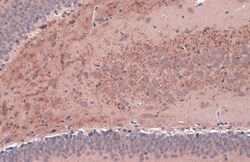

Keep as concentrated solution. Predicted reactivity: Mouse (100%), Rat (100%), Dog (100%), Cat (100%), Pig (100%), Chimpanzee (100%), Bovine (100%). Positive Control: mouse brain, rat brain, BDNF-transfected 293T. Store product as a concentrated solution. Centrifuge briefly prior to opening the vial.

| Immunohistochemistry (Frozen), Immunohistochemistry (Paraffin), Western Blot, Immunocytochemistry | |

| Human, Mouse, Rat | |